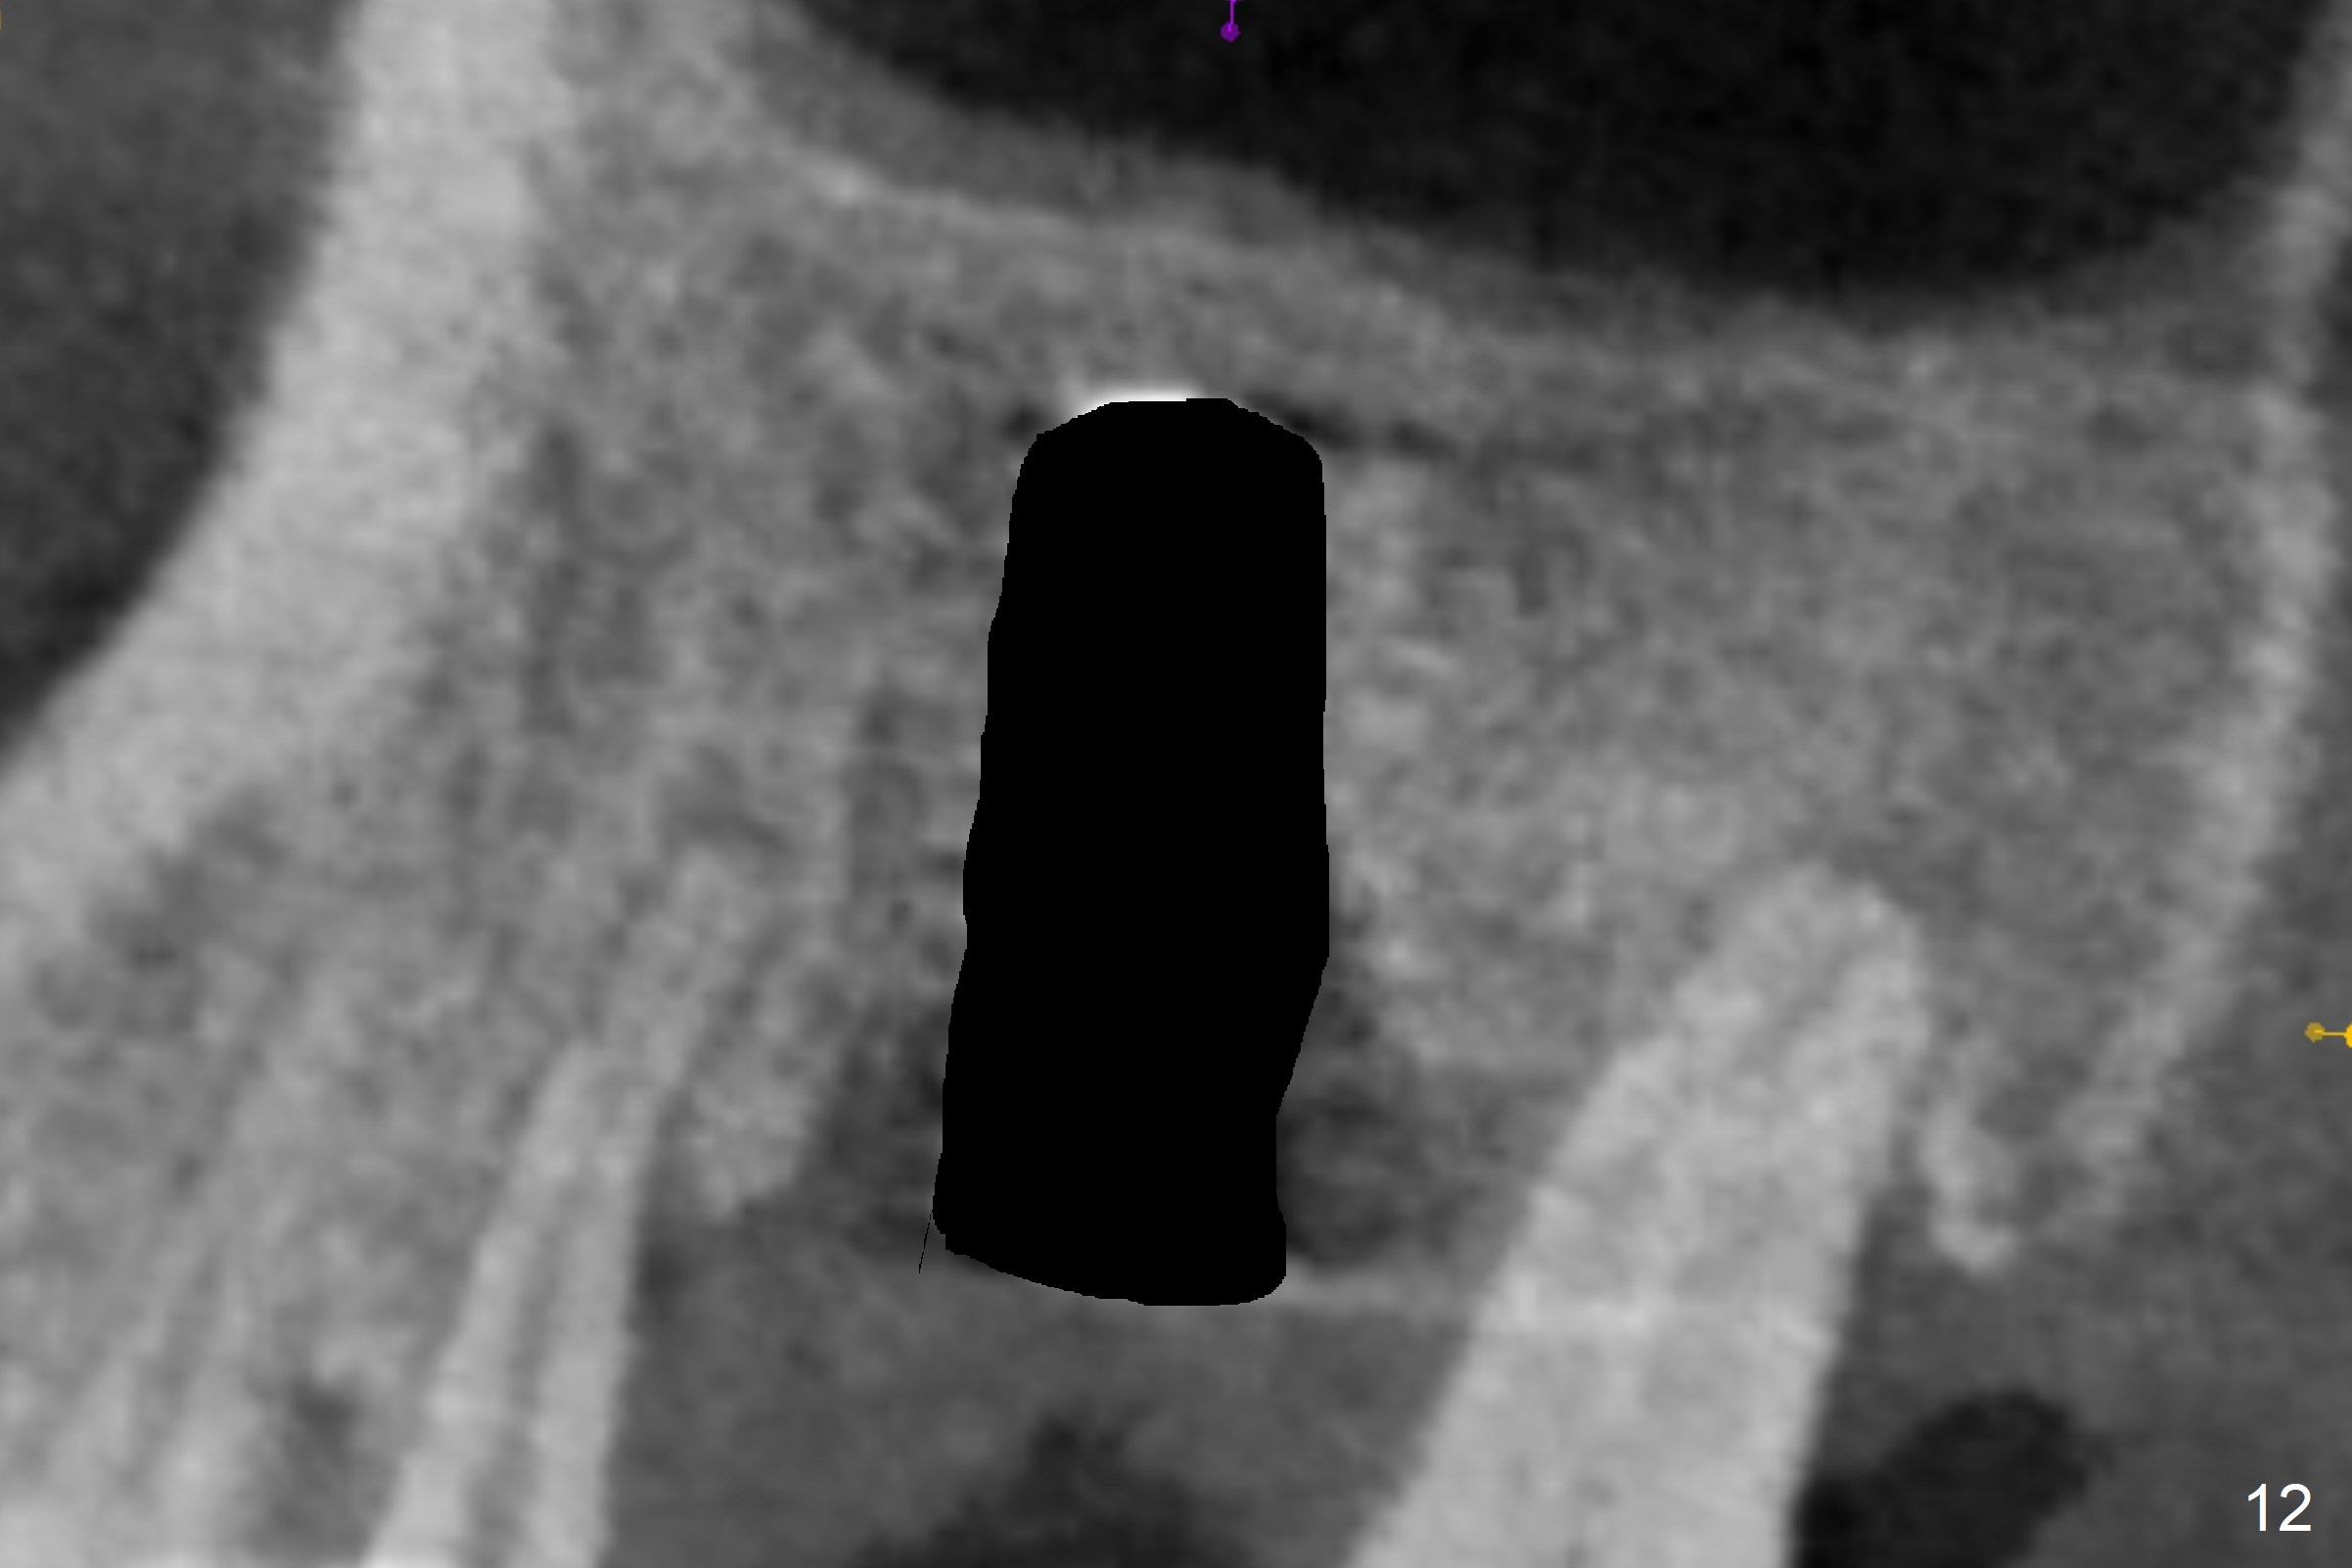

The amount of the bone graft mesial and distal the implant seems to reduce 3 and 4 months postop, respectively (Fig.6,7 arrowheads). When the acrylic is cut off 4 months postop, the bone graft is loose. The gingiva is unhealthy. The abutment and implant are loose. A healing abutment is placed (5x4 mm). The implant is torqued to 35 Ncm 6 months postop with the healing abutment reapplied. The patient will return for follow up nearly 9 months postop. A larger healing abutment will be used if the implant is stable. Two weeks later, use a smaller restorative abutment for easy impression. In fact the implant is unstable with #15 mesial shift due to abnormal occlusion with #17 (Fig.8). Bone density around the implant is low (* in Fig.9 (PA), 10,11 (CT sagittal, coronal sections)). A healing screw is placed for self healing. A 2nd option is to remove the implant (Fig.12), BEB (Fig.13) and place the implant deeper (Fig.14) or larger one (5.5-6.5x13 mm). The 3rd option is to place larger and longer implants (Fig.15 (tapered), 16 (cylindrical)). The implant access has partially closed 14 months postop, but there is a small buccal opening with sanguine exudate. Incision reveals severe bone loss around the implant; the mobile tooth #15 is extracted (Fig.17). After debridement and irrigation with normal saline, Vera Graft (Fig.18 *) and Collagen plug are placed with periodontal dressing.